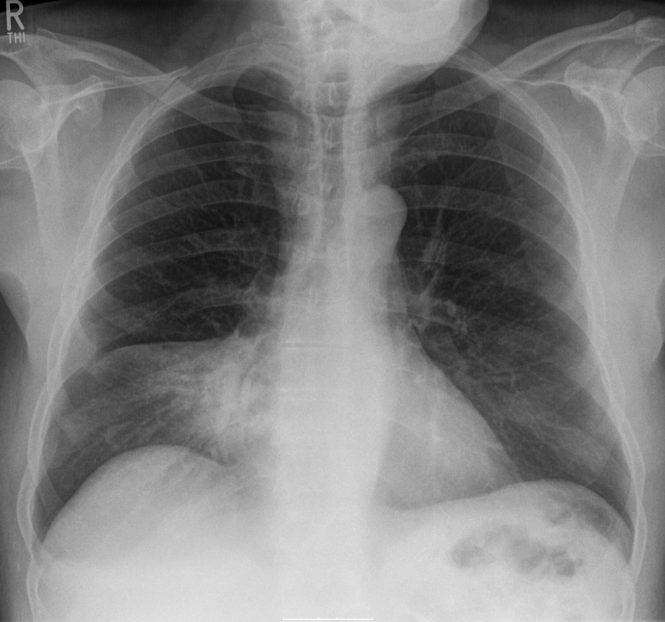

Hellerhoff / Wikipedia

Udało się wyhodować sztuczne płuca, które pracują.

Ponieważ tkanka płucna  właściwie się nie regeneruje, poważne schorzenia płuc są niezwykle trudno wyleczalne i najczęściej jedynym lekarstwem jest transplantacja. Z tym jednak, jak z innymi organami do przeszczepu, zawsze jest problem z racji niedostępności dawców. Naukowcy postanowili więc wyhodować tkankę płucą in vitro, a nastepnie tak zregenerowane płuca wszczepić pacjentowi. Na razie szczurowi. Udało sie to na Uniwersytecie Yale, o czym donosi najnowsze (25.06.2010) wydanie czasopisma Science. Najpierw z pobranych szczurzych płuc wycięto istniejący komponent komórkowy, pozostawiając jednak główną strukturę organu, a więc naczynia krwionośne oraz kanały, którymi powietrze jest w płucach transportowane. Powstało coś w rodzaju bezkomórkowego łożyska płucnego, które następnie umieszczono w specjalnym bioreaktorze, symulujacym warunki, w których płuca rosną w płodzie. Po wielu dniach hodowli udało się wytworzyć brakujące komórki, a gdy następnie szczurowi wszczepiono - na dwie godziny - tak bioinżynieryjnie zmodyfikowany organ, zaczął on prawidłowo pracować. Nowe płuca dokonywały przemiany tlenu i dwutlenku węgla oraz natleniania hemoglobiny we krwi. To pierwszy istotny krok. Potrzeba jednak jeszcze wielu dlaszych badań, by zdobyć  pewność, że  ta procedura będzie skuteczna na dłuższą metę i że będzie można zastosować ją u ludzi.